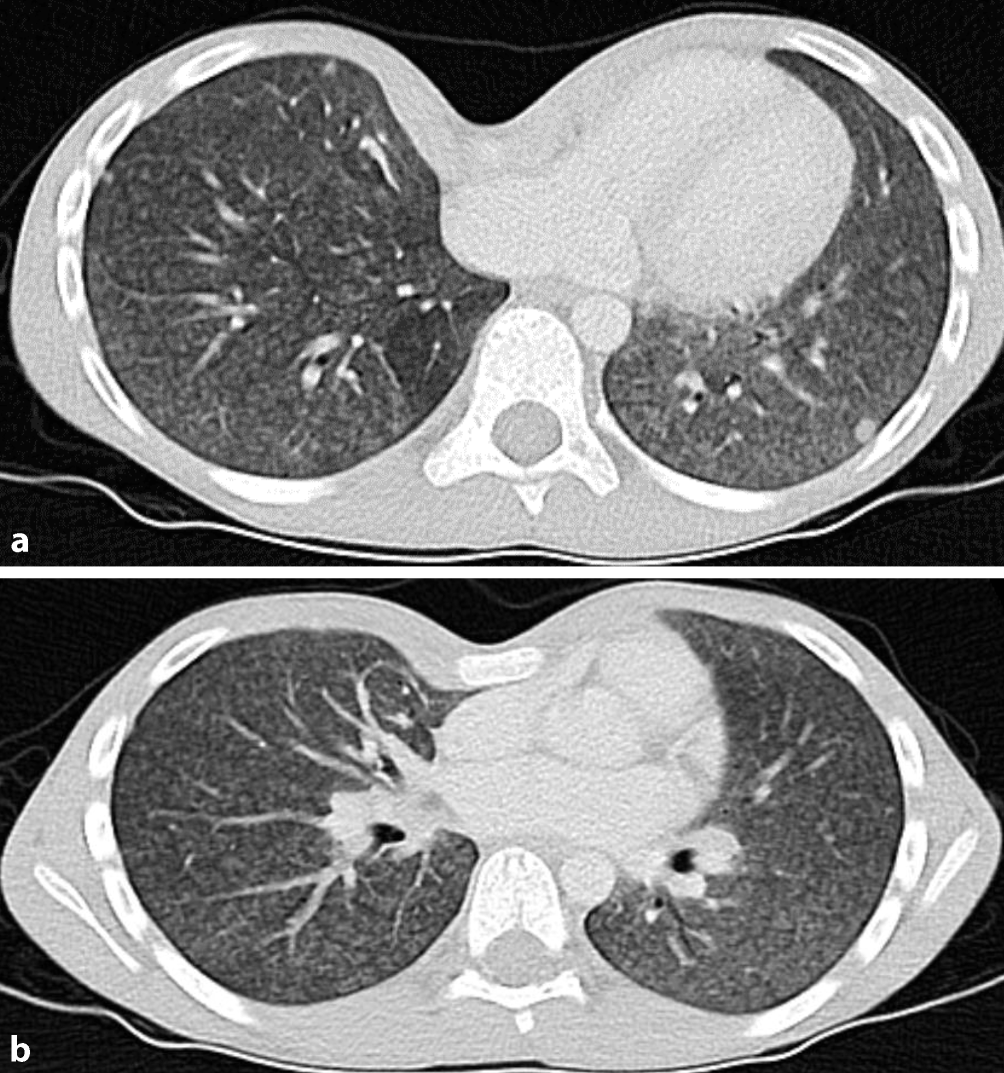

Die im Verlauf veranlasste Schnittbildgebung mittels Computertomographie (CT) detektierte bipulmonal ubiquitäre zentrilobuläre Milchglas-Noduli, multiple Rundherde und ein angedeutetes Air-Trapping (Abb. 2).

Abb. 2

Computertomographie (CT) Thorax vom 3. stationären Tag mit angedeutetem Air-trapping (a) und multiplen Noduli (b)

Der Nachweis von spezifischem IgG ist einzig beweisend für eine Exposition gegenüber einem Allergen, ein positiver Test bestätigt jedoch nicht die Diagnose einer Hypersensitivitätspneumonitis [2, 15]. In der bronchoalveolären Lavage ist das Vorliegen einer Lymphozytose diagnostisch hinweisend, bei der nicht-fibrotischen Form ist zudem die CD4- zu CD8-Ratio erniedrigt [2, 3, 5, 14]. Im Kindesalter wird auf die Durchführung von Biopsien und bronchialen Provokationen in aller Regel verzichtet [5, 15, 16]. Initial kann ein Röntgen-Thorax bei bis zu einem Drittel der Patient:innen normal ausfallen. In der Computertomographie des Thorax können bei der nicht-fibrotischen Form Milchglastrübungen und Mosaikmuster sowie – in Exspirationsaufnahmen – Air-Trapping dargestellt werden. Spezifisch ist zudem das Vorliegen des „three density pattern“, ein Nebeneinander von drei unterschiedlichen Densitäten. Bei der fibrotischen Hypersensitivitätspneumonitis finden sich zusätzlich fibrotische Veränderungen mit Retikulationen, Traktionsbronchiektasen und Honigwaben [2, 5, 8, 13, 14].